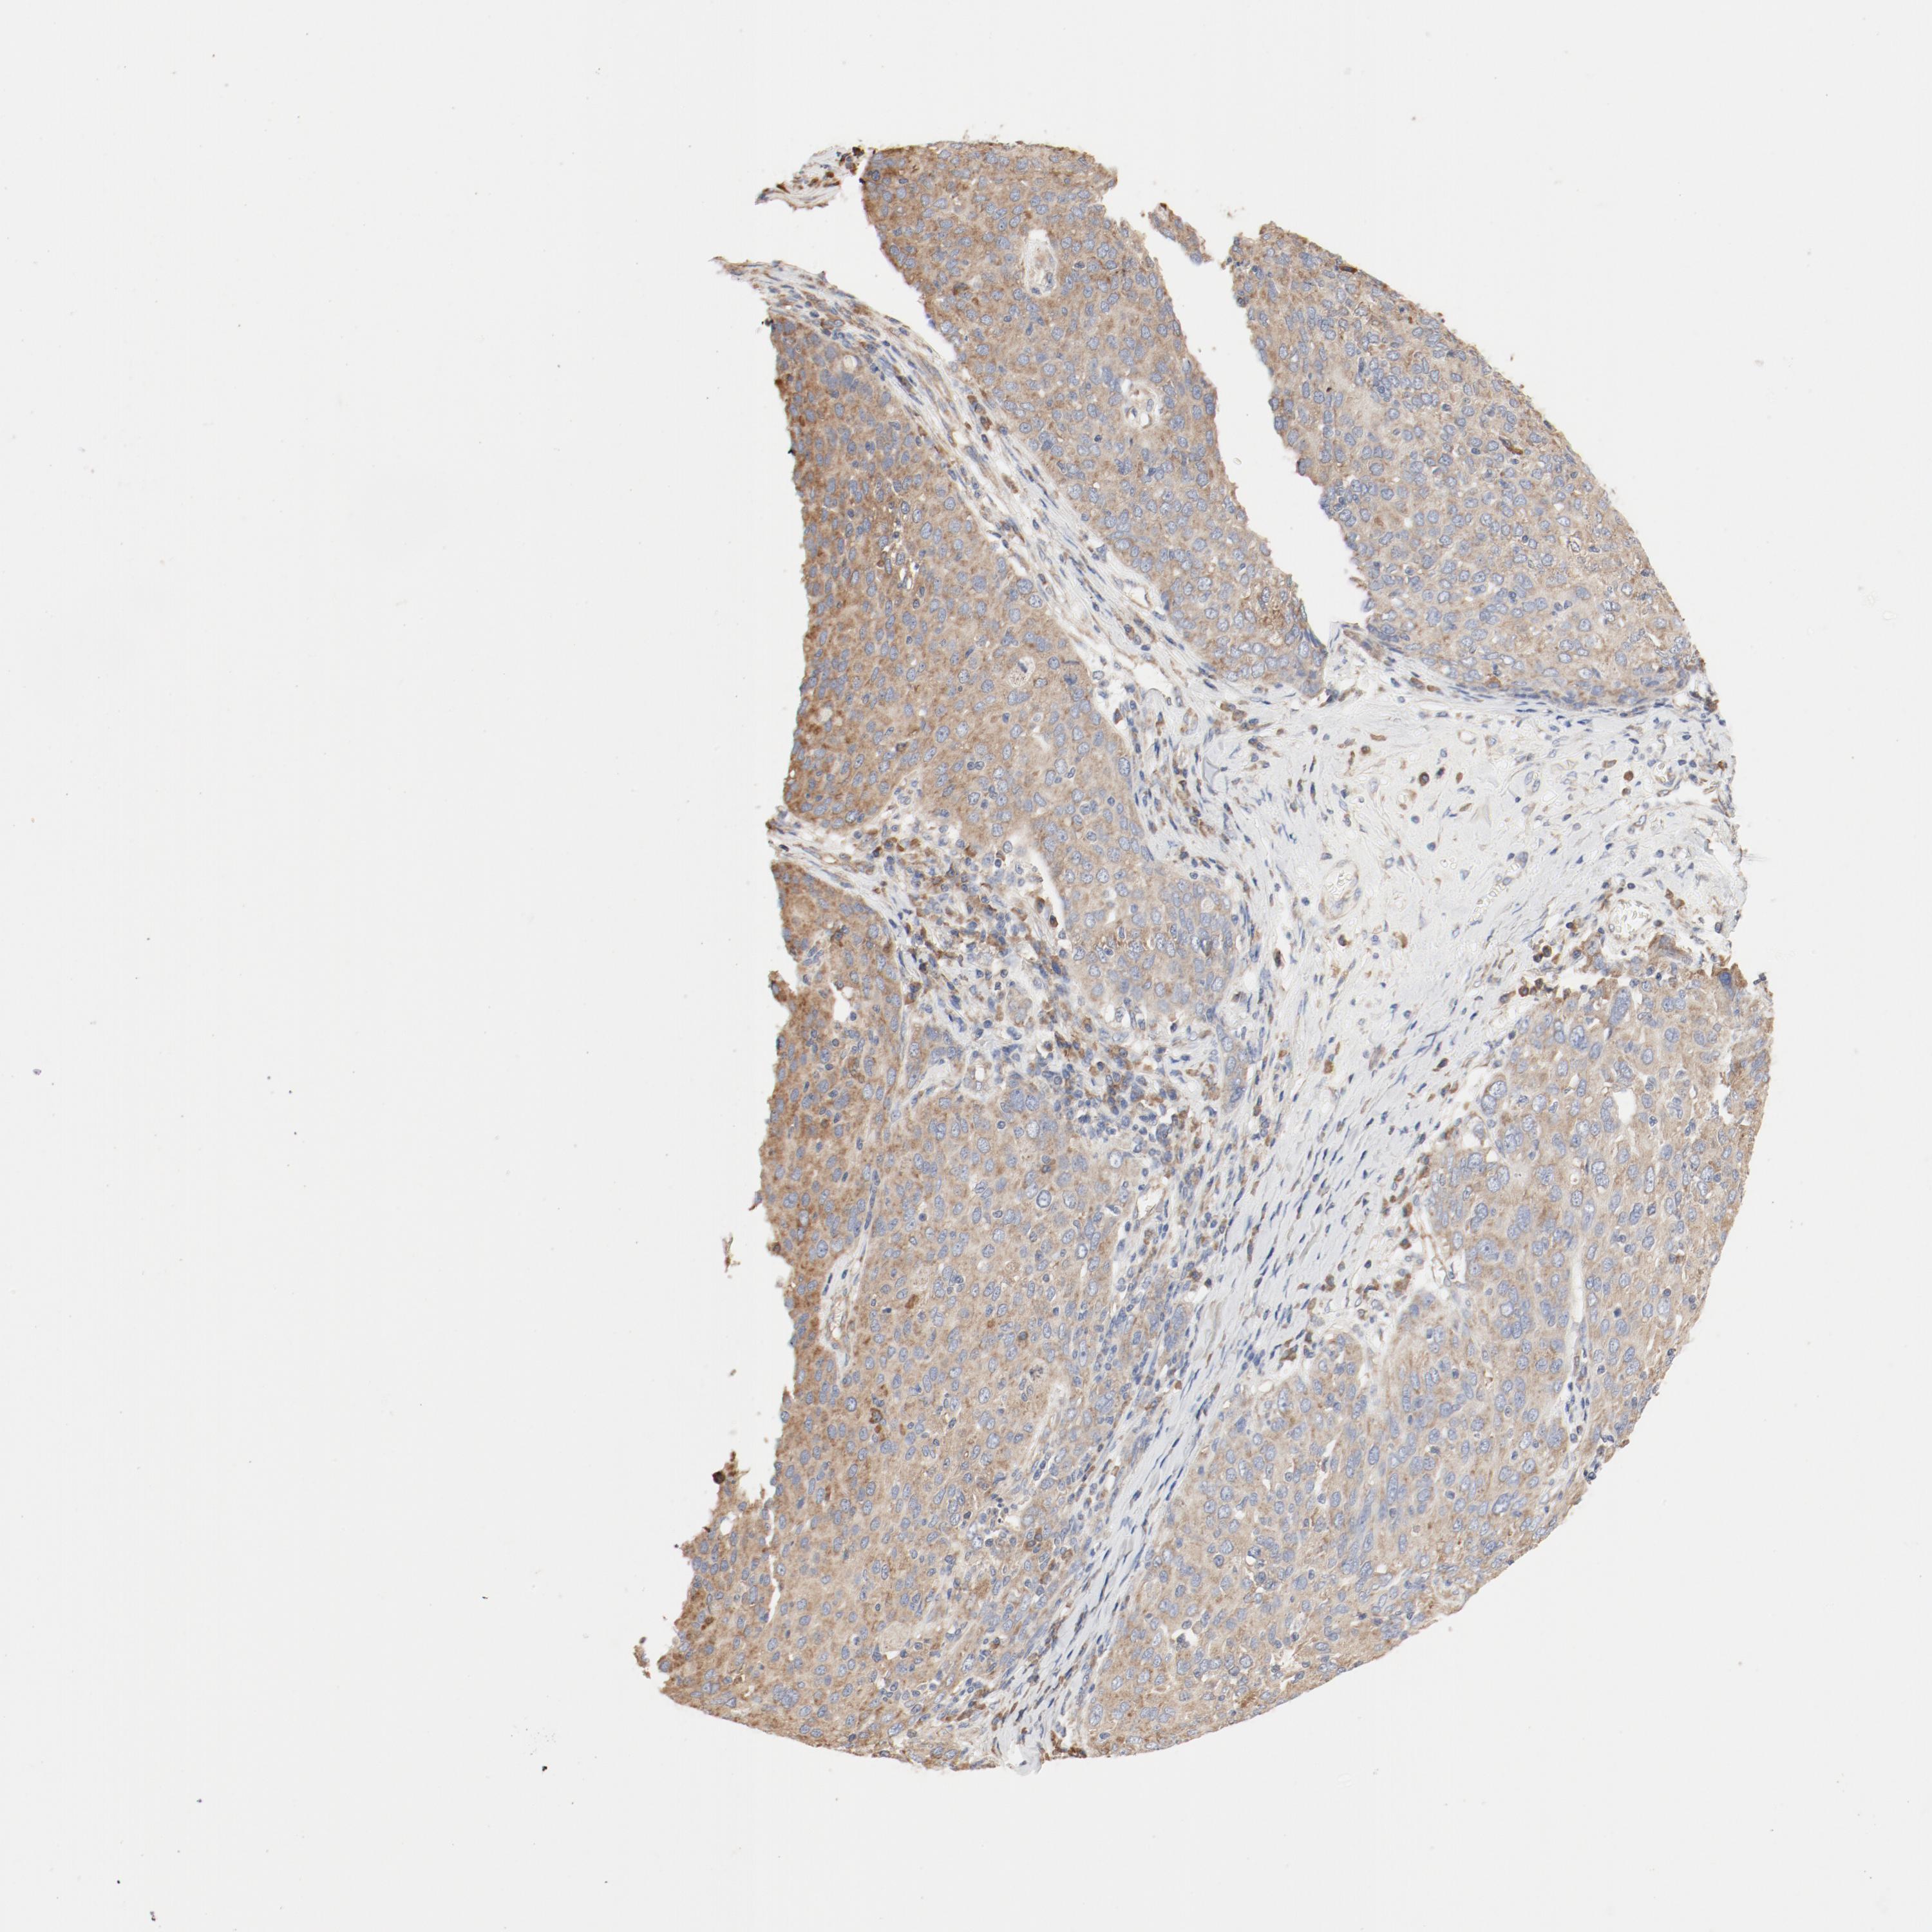

OVARIAN CANCER - Protein expressioni

A mouse-over function shows sample information and annotation data. Click on an image to view it in a full screen mode. Samples can be filtered based on level of antibody staining by selecting one or several of the following categories: high, medium, low and not detected. The assay and annotation is described here.

Note that samples used for immunohistochemistry by the Human Protein Atlas do not correspond to samples in the TCGA dataset.

Antibody stainingi

Antibody staining in the annotated cell types in the current human tissue is reported as not detected, low, medium, or high, based on conventional immunohistochemistry profiling in selected tissues. This score is based on the combination of the staining intensity and fraction of stained cells.

Each image is clickable and will lead to virtual microscopy that enables deeper exploration of all samples and also displays staining intensity scores, fraction scores and subcellular localization as well as patient and tissue information for each sample.

Antibody HPA031153

Antibody CAB004027

Cystadenocarcinoma, serous, NOS

Carcinoma, endometroid

Cystadenocarcinoma, mucinous, NOS

Carcinoma, NOS